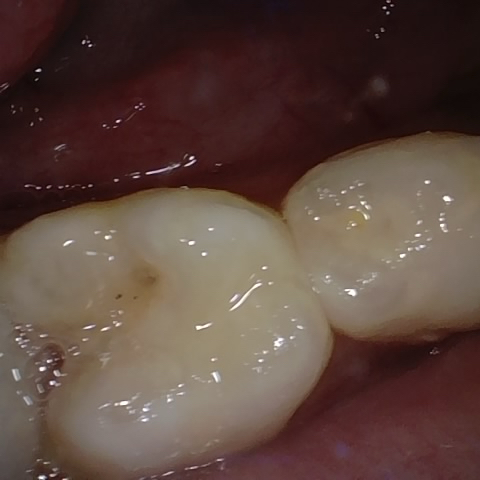

Annotated as "Good"